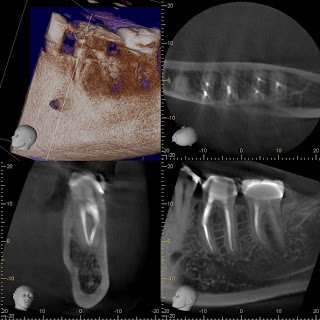

A CBCT was taken to evaluate the separation in 3D. This image was very helpful because it told us the anatomy of the mesial root. It shows clearly that the mesial root is a single root, rather than two separate roots. With this information, we can plan to remove some tooth structure between the MB and ML canals in our attempt to access and remove the separated instrument. It also showed us that there were 2 separated instruments in the MB canal. This information is crucial in our ability to remove the spearated instrument. (The radiographic imaging also warned us not to remove any dentin mesial to the prepared space to prevent root perforation)

This treatment can only be accomplished with the use of the dental operating microscope and use the of ultrasonic instrumentation. Approximately 1 hour of treatment time was used in removing the separated instruments.